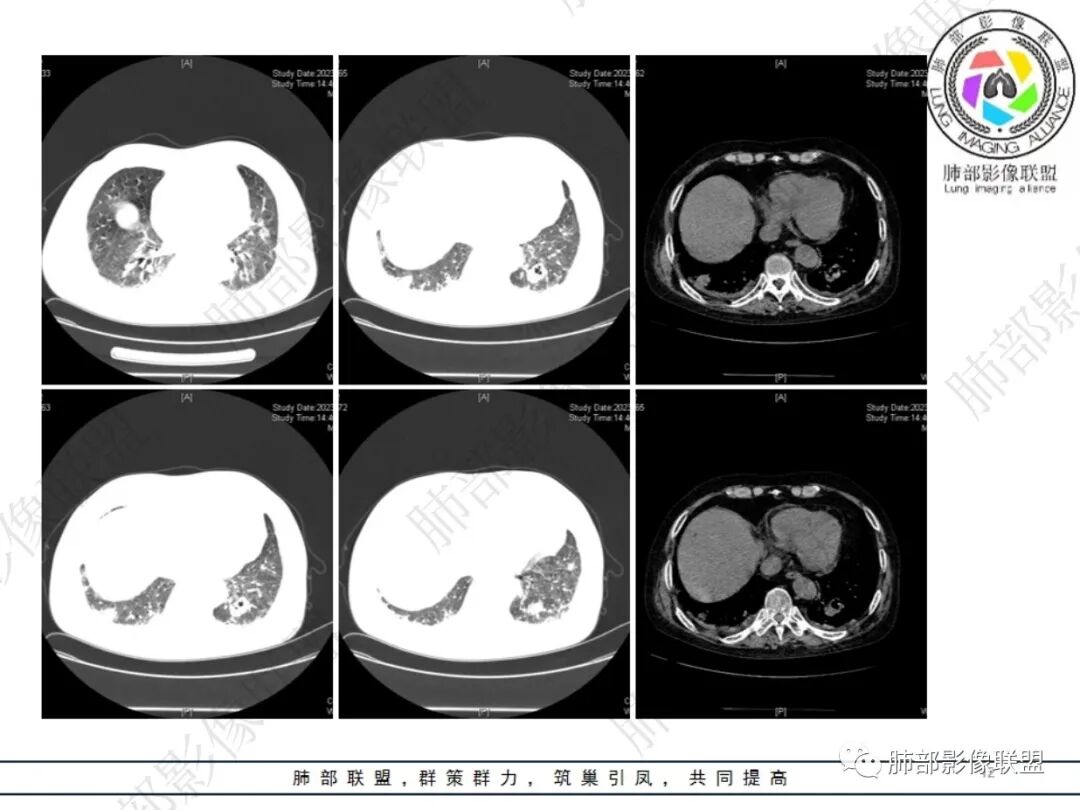

六、影像学表现:

①局限或弥漫肺部浸润影,可为GGO、斑片影、大部分以实变为主。

②单个或多个结节、团块影,结节大小不等,可见粟粒性结节。大部分为较大结节,易形成空洞。

③空洞:较为常见。

④累及胸膜,出现胸腔积液。